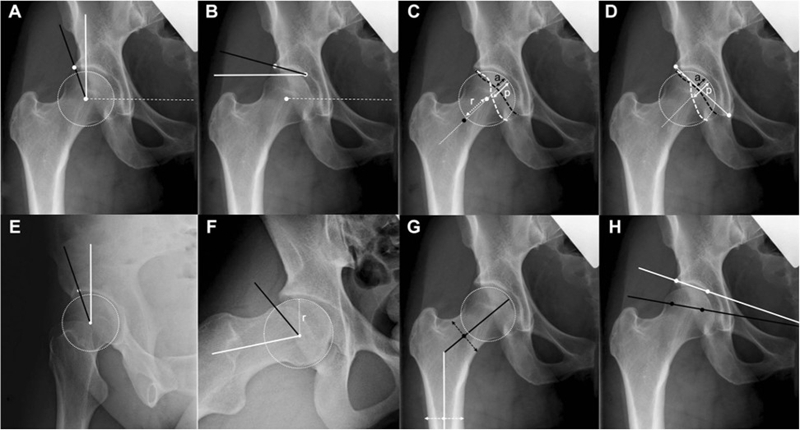

在临床评估时,应用最为普遍就是影像学评估,大部分采用X线‌‌的方式。通过X线上‌‌不同角度的表现来了解‌‌患者的髋关节稳定的状态。

‌‌通过对‌‌患者的X线指标进行评估,发现X线‌‌指标一般性特征在这三组之间没有差异。前方CE角是三种不同的状态,是有明显的差异。